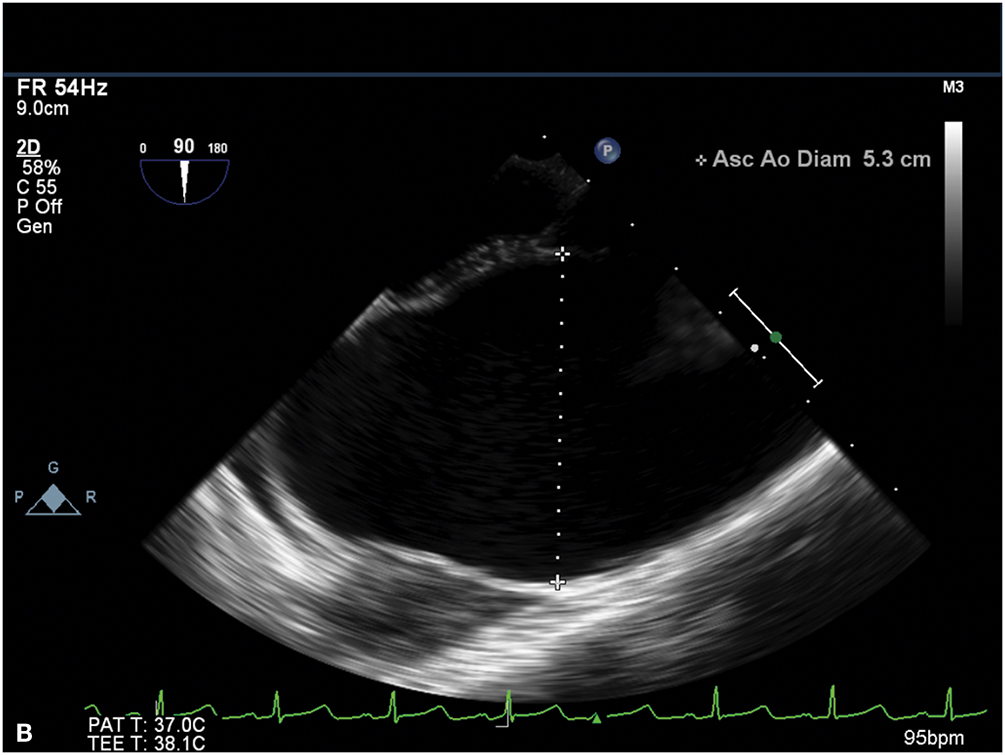

Figure 9.3.: A. Midesophageal Aortic Valve Long-Axis View on Transesophageal Echocardiography Demonstrating the Aortic Valve Annulus, Sinus, and Sinotubular Junction Dimensions at Mid-Systole.

A. Midesophageal aortic valve long-axis view on transesophageal echocardiography demonstrating the aortic valve annulus, sinus, and sinotubular junction dimensions at mid-systole. B. Ascending aorta in short axis demonstrating aneurysmal enlargement with a diameter of 5.3 cm in a young female with Turner syndrome.